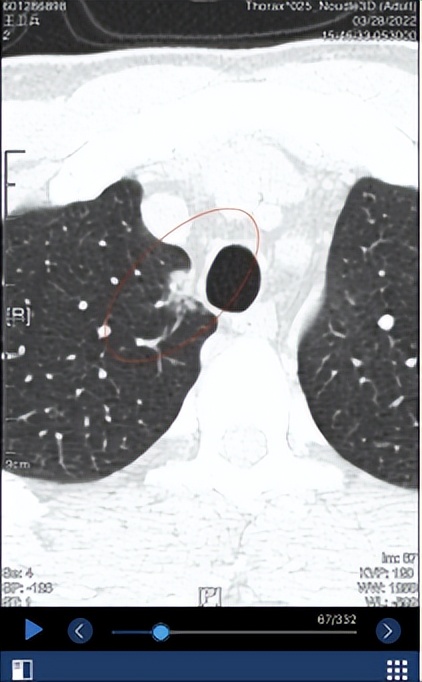

3. 2022.1.26日复查,SE4/7IMG70右肺上叶尖段见一混合密度影,病灶形态类圆形,边界不清晰,无分叶,有毛刺,有胸膜牵拉,无血管束集征,无空泡征。病灶前后径 12.6 mm,左右径 8.8 mm,上下径 18.7 mm。病灶平扫时密度为 -88HU。左肺下叶后基底段(SE4/7,IM205)见一枚磨玻璃结节,内见空泡影,长径约6mm。 右肺中叶及左肺上叶舌段少许斑片索条影。 两肺门区未见异常密度影。 胸膜未见增厚改变。 纵隔内未见异常密度影。